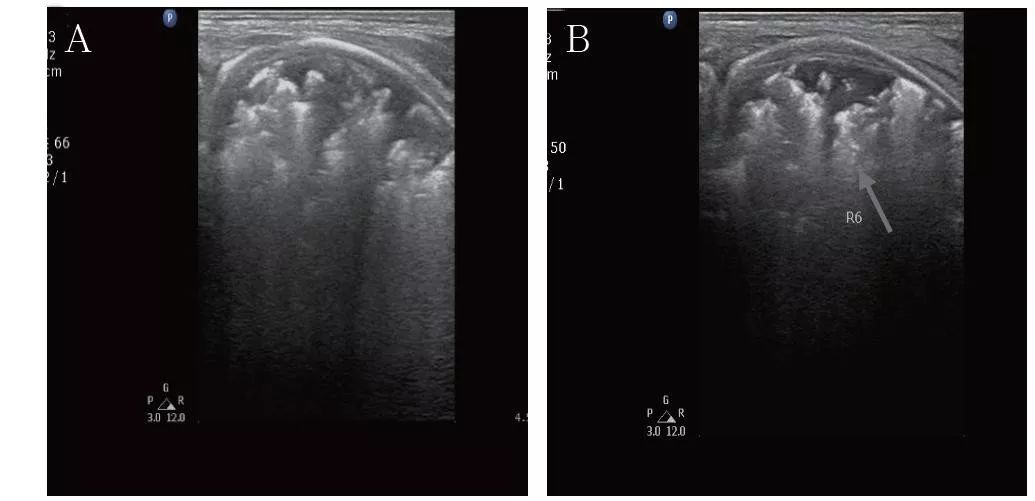

出生后15天:进行了肺部超声检查。A.广泛弱回声实变区;B.胸膜线变细、中断。